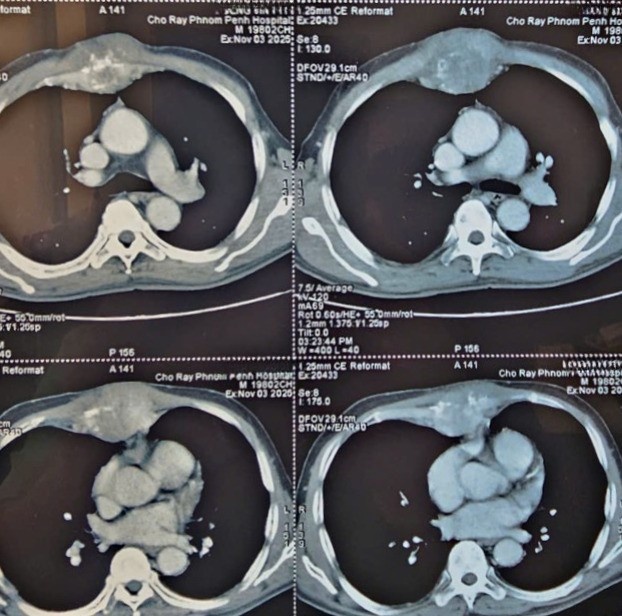

Kết quả chụp CT có tiêm thuốc cản quang cho thấy khối u xương ức kích thước 6x8,8 cm có tính chất ác tính, kèm phá hủy xương; đồng thời xuất hiện tổn thương tại xương sườn phải số VII và thân đốt sống L1 nghi di căn xương.

Không dừng lại ở đó, hình ảnh còn ghi nhận nhiều tổn thương gan bắt thuốc cản quang, bờ gan không đều gợi ý xơ gan, cùng tình trạng xơ hóa và thâm nhiễm nhu mô phổi hai bên kèm nhiều kén khí.

| Hình ảnh chụp CT của bệnh nhân được thực hiện tại Bệnh viện Chợ Rẫy Phnom Penh. |